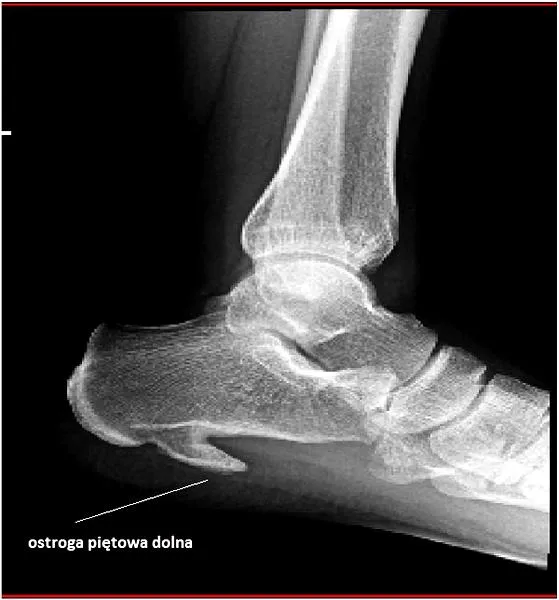

Ostroga piętowa staje się zmorą wielu biegaczy, a ja niestety również musiałem się z nią zmierzyć. To schorzenie objawia się ostrym bólem pięty, który odczuwam głównie rano, kiedy stawiam pierwsze kroki po dłuższym odpoczynku. Jeżeli cię to ciekawi, sprawdź, czy ból gardła przeszkadza w bieganiu. W takich momentach czuję, jakbym chodził po kawałkach szkła, co stanowi naprawdę niezbyt przyjemne doświadczenie. Takie dolegliwości potrafią skutecznie zrujnować zarówno moje treningi, jak i radość z biegania. Dlatego niezwykle istotne staje się zrozumienie tego problemu oraz podjęcie odpowiednich działań.

- Ostroga piętowa to powszechna dolegliwość wśród biegaczy, powodująca ostry ból pięty.